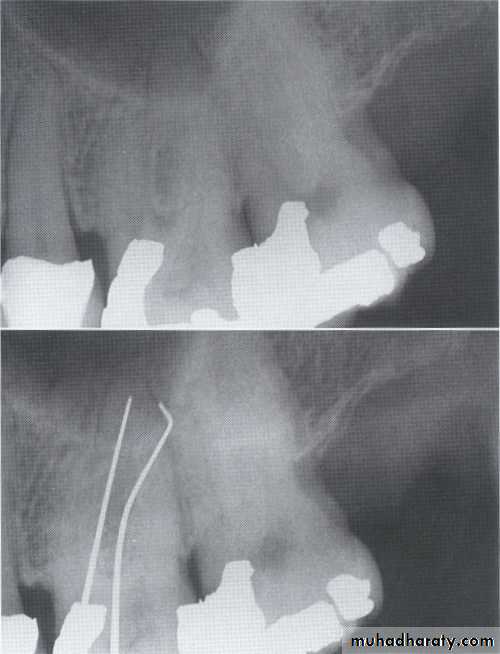

Visualization of the depth of pockets

may be aided by inserting a gutta-percha

point.

3.Furcation involvements:

Bone loss in the furcation area of the roots which is evidence of advanced disease in multirooted

teeth.

Initially seen as widening of the PL space at the crest of

the furcation . As lesion progresses, the bone

loss progresses apically.

Mild/moderate/sever.